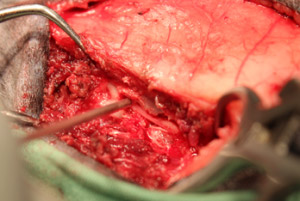

胸椎12番目と13番目の椎間にて重度の椎間板逸脱が確認されました。また、脊髄を右側から重度に圧迫していたため、手術適応と判断し、片側椎弓切除手術を行い、圧迫している椎間板物質を摘出する手術を行いました。

- まず背側の棘突起に沿って切開、多裂筋を分離し、関節突起を露出し、関節突起を除去後、片側椎弓板をラウンドバーにてバーリングし造窓しました。

- ケリソンパンチにて頭側尾側に造窓の拡張を行いました。

-

脊髄を露出し逸脱した椎間板を摘出しました。後は閉創し術式は以上で終了となります。 術後は約2ヶ月でほぼ以前と変わらず歩けるようになりました。飼い主様が熱心にリハビリをして頂いた結果、症状は重度でしたが無事完治することができてホッとしています。ミニチュアダックスは椎間板ヘルニアになる子が多く、予防としてソファーや階段などで自由に遊ばせないことが重要です。 今では元気に走り回ってます。